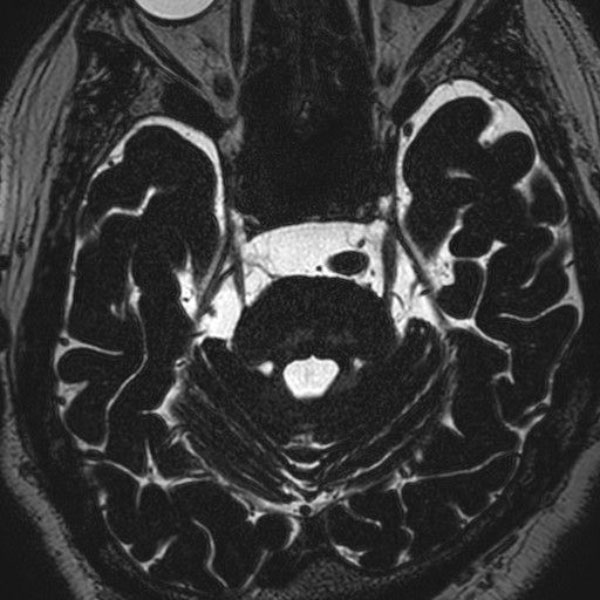

手術前

(MR1)